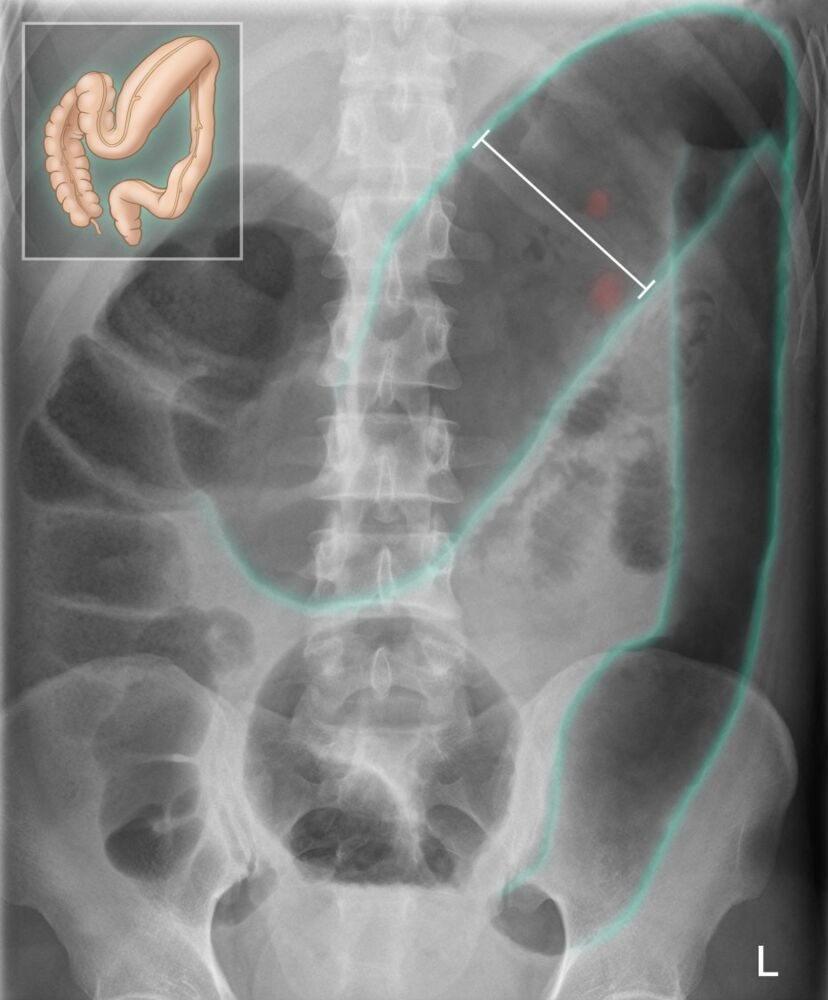

• Plain X-ray or CT scan showing marked colonic dilation, loss of haustra, and possible mucosal ulceration

• X-ray or CT scan: Colonic distention (> 6 cm dilation of the right colon and > 9 cm in cecum), loss of normal haustral pattern, irregular mucosal pattern with areas of ulceration alternating with areas of edema.